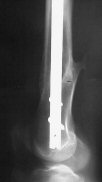

THX, initial images are

1,

2.

At that moment we had in stock only the 10 mm solid nails so of course there was no idea about early weight bearing. But it was quite enough for early knee ROM excersises (see attached). Two locking screws through the distal block provided that.